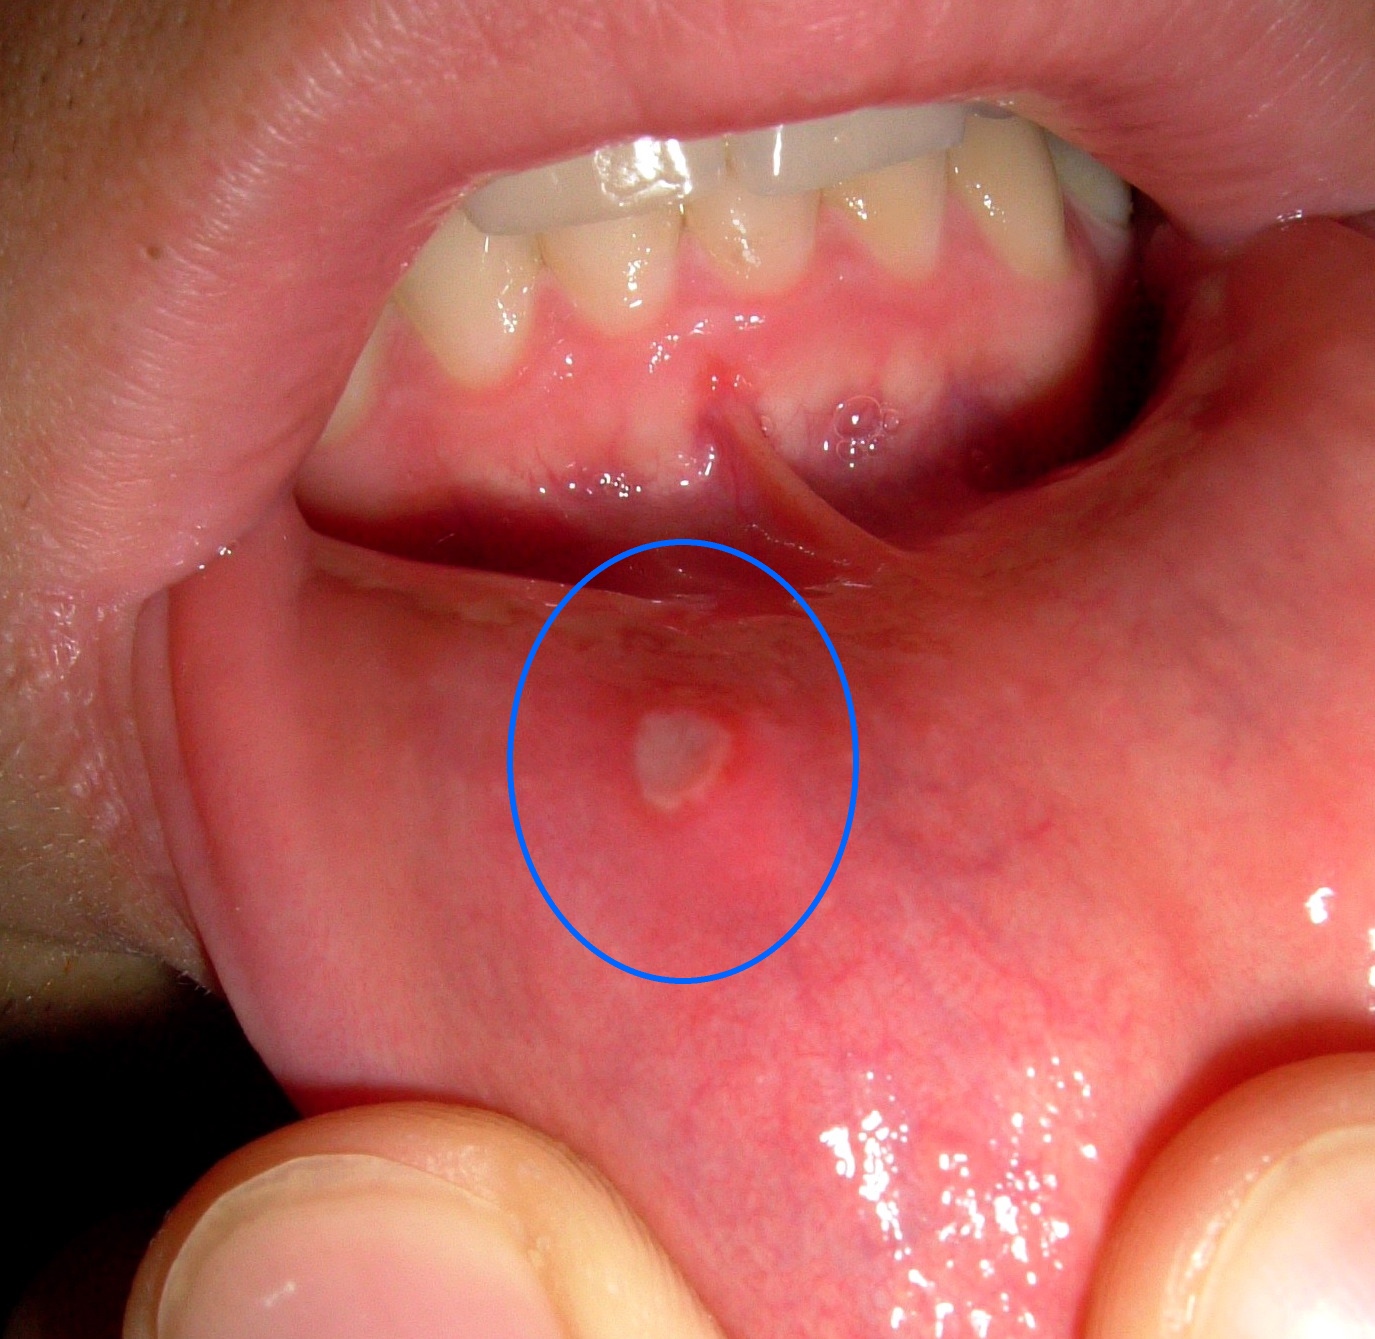

LILO POST: Mouth sores Pictures

Mouth sores. Causes, symptoms, treatment Mouth sores

Mouth Sores Pictures | Fever Blisters In Mouth | How To …

inside mouth herpes treatment, bubble inside mouth, herpes inside your mouth, blister inside your mouth, blisters around mouth and inside, mouth blisters fever all over, high fever blisters in mouth